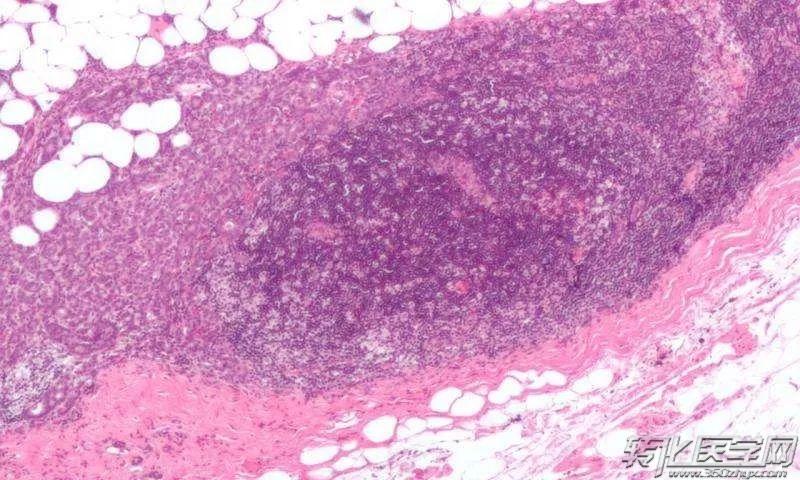

研究人员对78例浸润性乳腺癌切除的患者进行深入的研究。他们不仅对患者的漱口水和尿液等进行检测以探明微生物组成情况,还对患者乳腺组织中的微生物进行深度挖掘。通过这项研究中,科学家首次发现健康乳腺组织中包含更多的甲基杆菌属,这一发现在未来可为抗击乳腺癌提供全新的视角。

除了关于甲基杆菌属的发现之外,研究小组还发现乳癌患者的尿样中革兰氏阳性菌(包括葡萄球菌和放线菌)的水平更高。这些细菌在乳腺癌中所起的作用需要进一步的研究来确认。